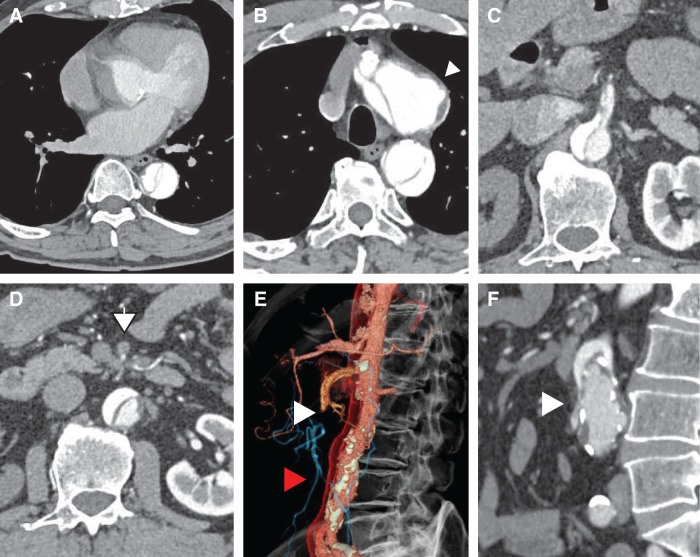

Case presentation: A 71-year-old male presented with acute chest pain and was diagnosed with Stanford Type A AAD extending to the abdominal aorta, with superior mesenteric artery (SMA) dissection leading to intestinal ischemia. To restore intestinal perfusion, emergency endovascular SMA stenting was performed as the initial intervention, followed by ascending aorta and total arch replacement using the frozen elephant trunk technique 12 hours later. The patient recovered without complications and was discharged ambulatory on postoperative day 20.